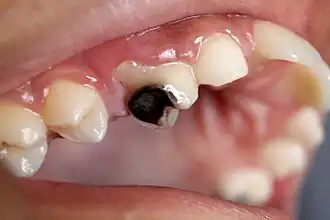

A person experiencing caries may not be aware of the disease.[12] The earliest sign of a new carious lesion is the appearance of a chalky white spot on the surface of the tooth, indicating an area of demineralization of enamel. This is referred to as a white spot lesion, an incipient carious lesion, or a "micro-cavity".[13]

As the lesion continues to demineralize, it can turn brown but will eventually turn into a cavitation ("cavity"). A lesion that appears dark brown and shiny suggests dental caries were once present, but the demineralization process has stopped, leaving a stain. Active decay is lighter in color and appears dull.[14]

As the enamel and dentin are destroyed, the cavity becomes more noticeable. The affected areas of the tooth change color and become soft to the touch. Once the decay passes through the enamel, the dentinal tubules, which have passages to the nerve of the tooth, become exposed, resulting in pain that can be transient, temporarily worsening with exposure to heat, cold, or sweet foods and drinks.[15] A tooth weakened by extensive internal decay can sometimes suddenly fracture under normal chewing forces. When the decay has progressed enough to allow the bacteria to overwhelm the pulp tissue in the center of the tooth, a toothache can result, and the pain will become more constant. Death of the pulp tissue and infection are common consequences. The tooth will no longer be sensitive to hot or cold, but can be quite tender to pressure.